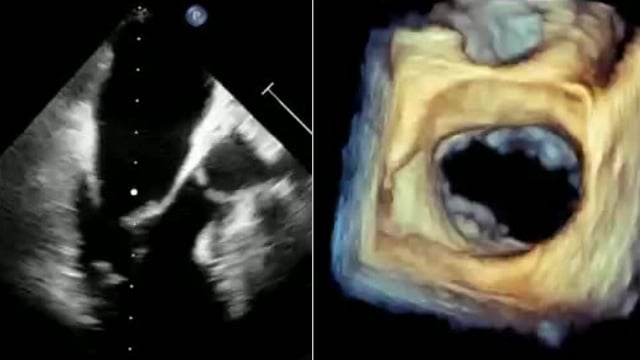

Tricuspid valve - How to evaluate?

This session offers a detailed evaluation framework for the tricuspid valve, encompassing clinical decision-making, anatomical assessment with 2D and 3D imaging, quantification of regurgitation, and differentiation of secondary and device-related tricuspid regurgitation, supported by advanced imaging software techniques.

Mitral valve - How to evaluate?

This educational session focuses on comprehensive evaluation of the mitral valve to guide clinical decision-making. Topics include risk stratification and patient selection for Mitral TEER, detailed anatomy review, assessment of primary and secondary mitral regurgitation phenotypes, advanced quantification techniques per current guidelines, and pre-intervention transoesophageal echocardiography...